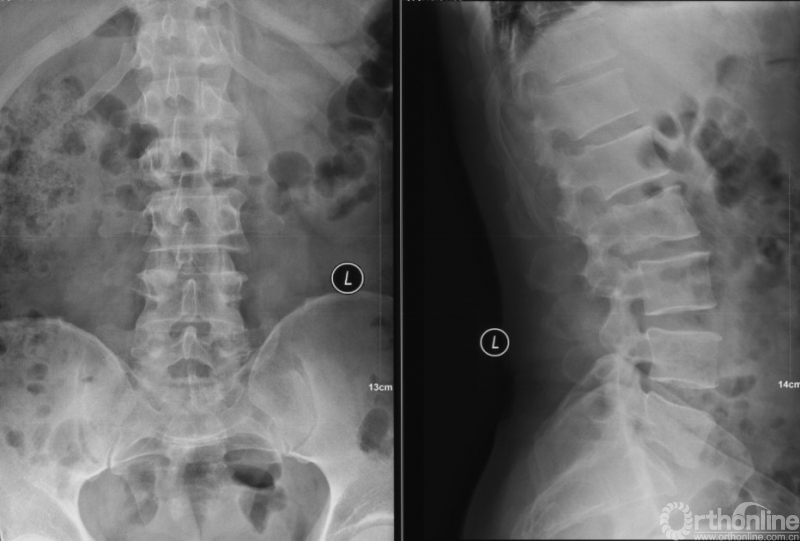

影像学资料

PVP治疗

术后6个月

入院影像学资料